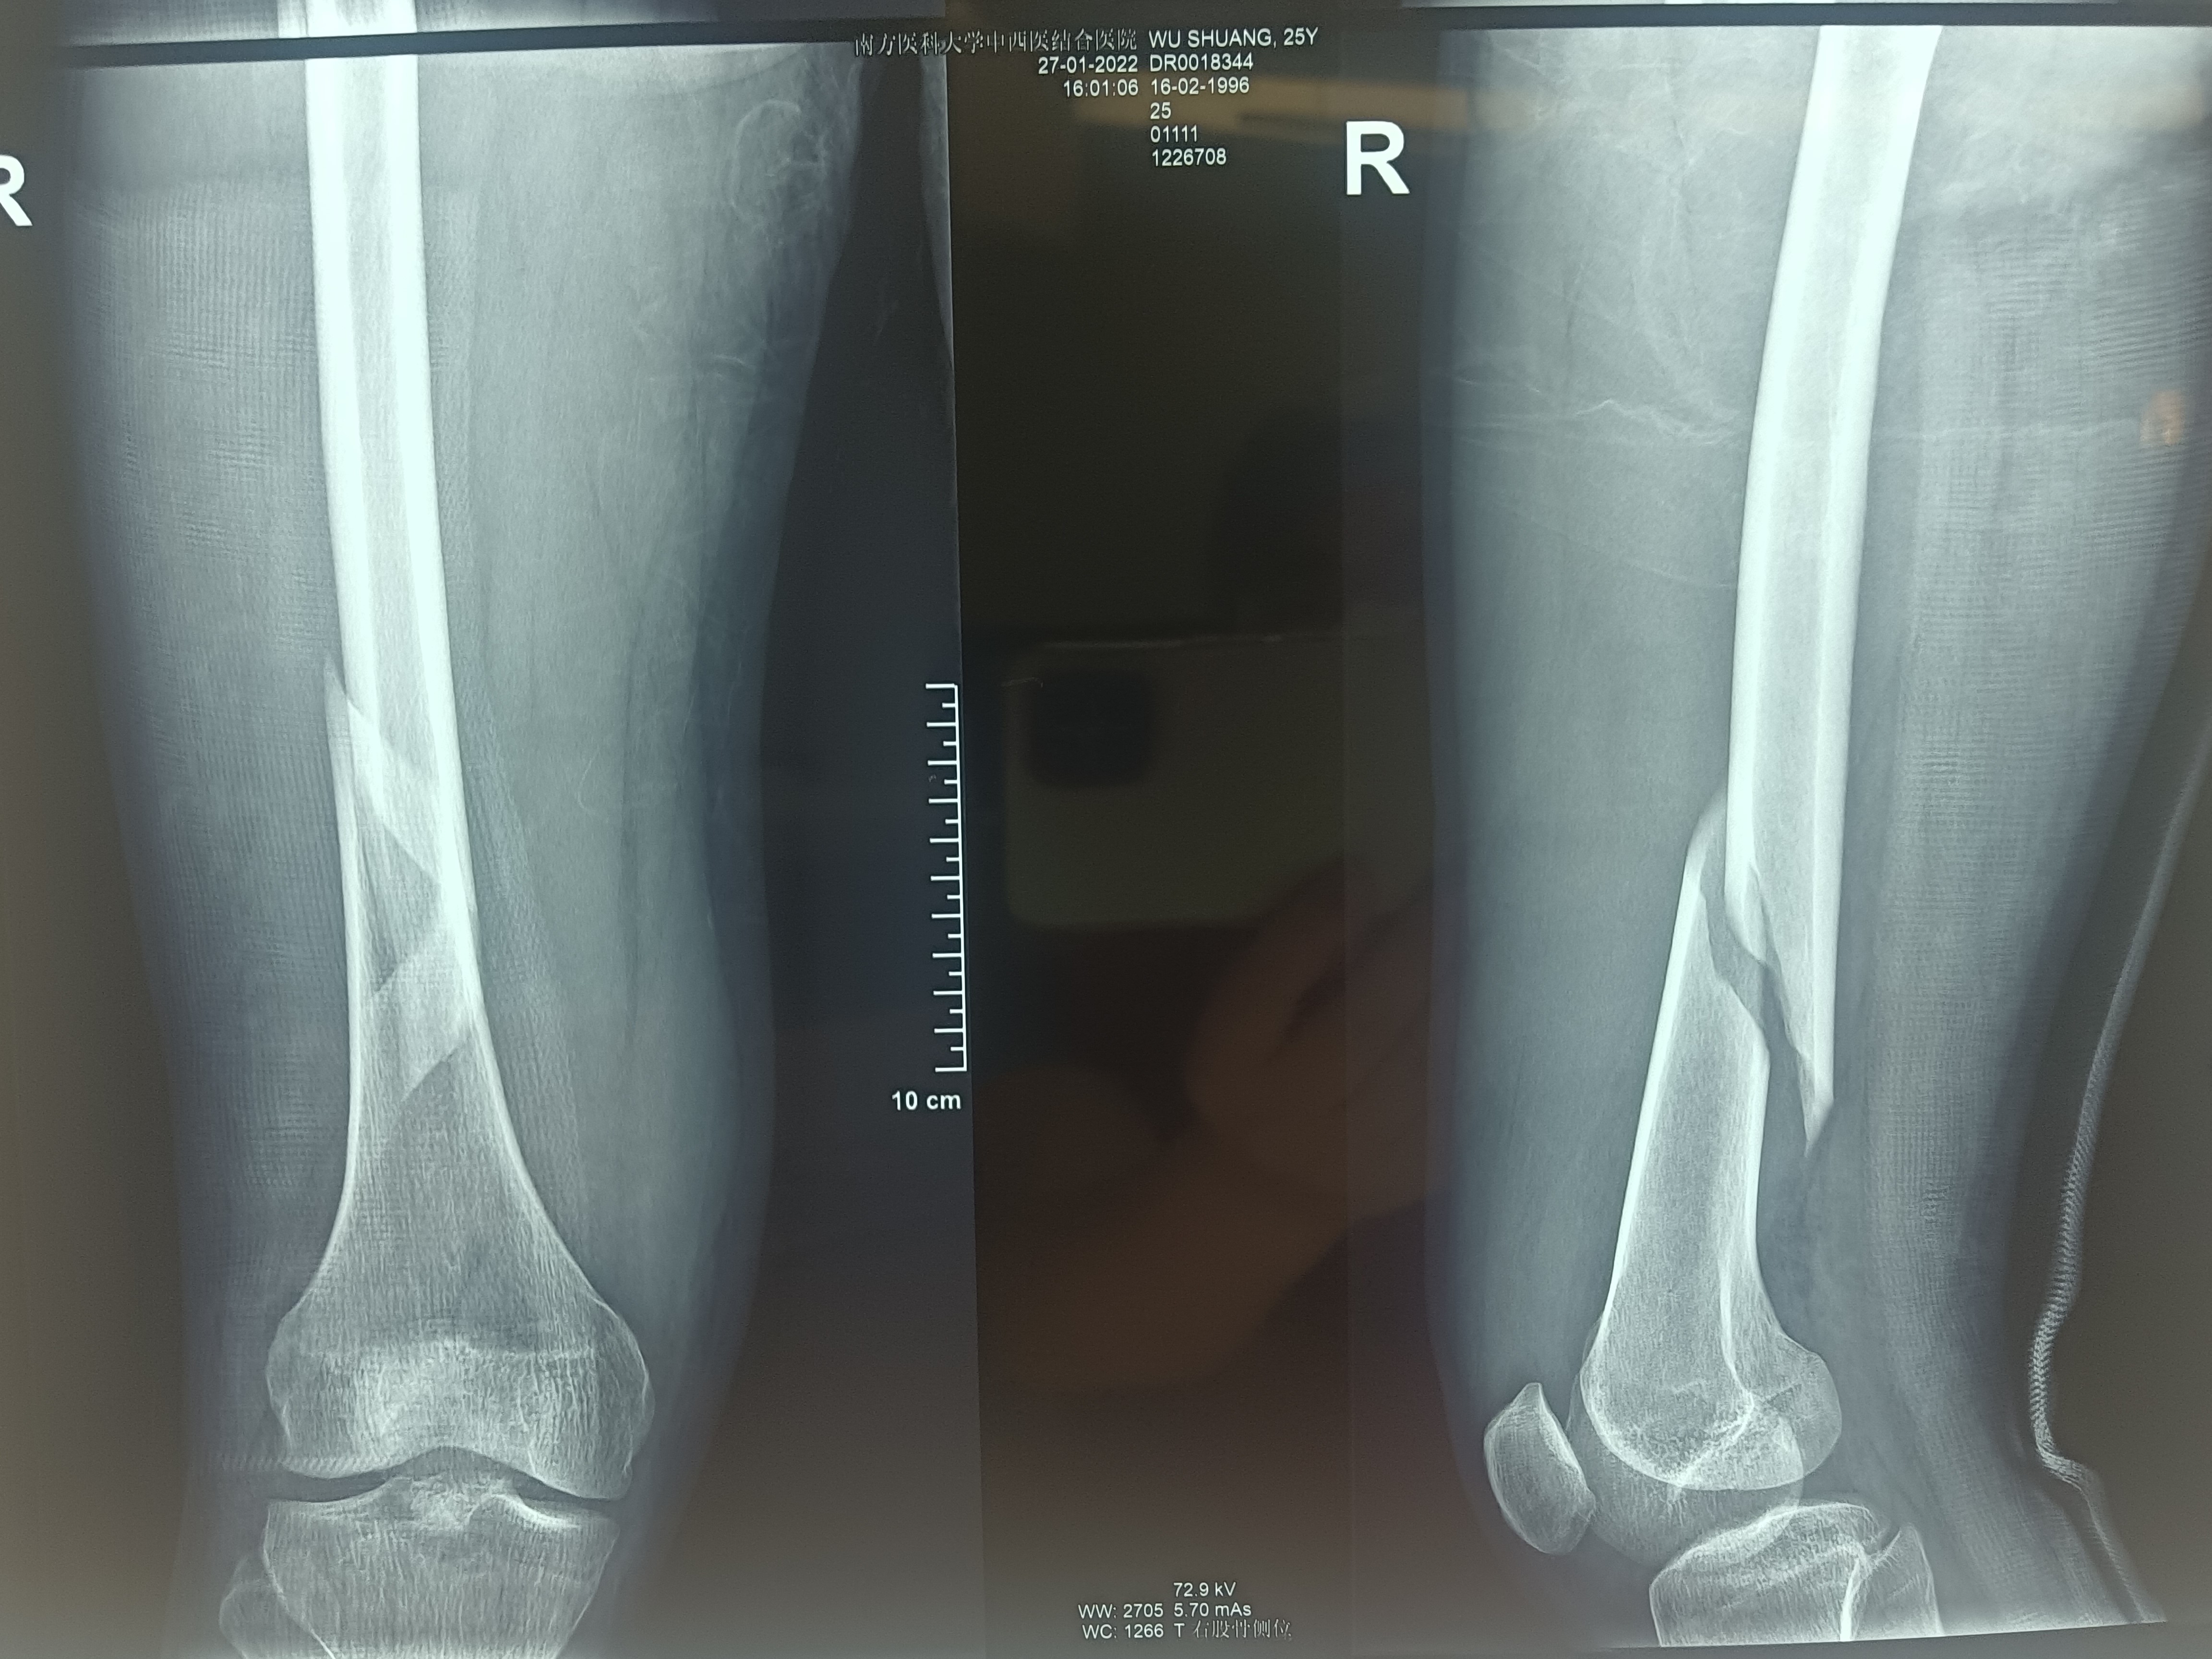

股骨下段螺旋性骨折

大年初二,王先生退热并且各项指标恢复正常,达到手术条件。术前,手术室杨嘉琪等护士为王先生精心摆好最合适的体位,在麻醉科医护人员的紧密配合下,骨伤科创伤足踝组组长徐楚江主任医师和科室骨干成功完成微创股骨干骨折闭合复位髓内针内固定手术治疗。